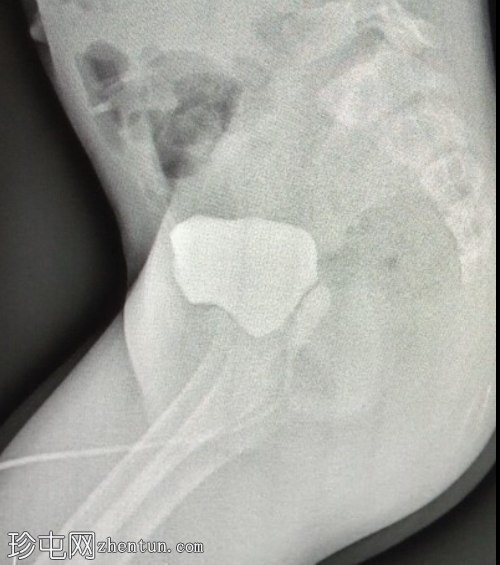

侧位

侧位影像显示膀胱后方可见一管状结构,可能为阴道,且充满造影剂。这提示膀胱与阴道之间存在共同的会阴开口。然而,这些影像并未显示该结构之间的瘘管连接。

该生殖器造影显示膀胱与阴道之间存在共同的会阴开口,符合持续性泌尿生殖窦的诊断。